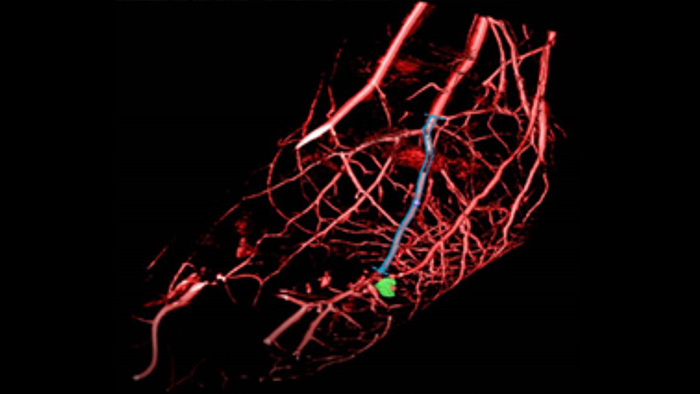

SmartCT Roadmap facilitates complex interventions by providing live 3D image guidance that can be segmented to emphasise target vessel and lesions, aiding navigation through complex vessel structures. All controlled via the touch screen at the table.